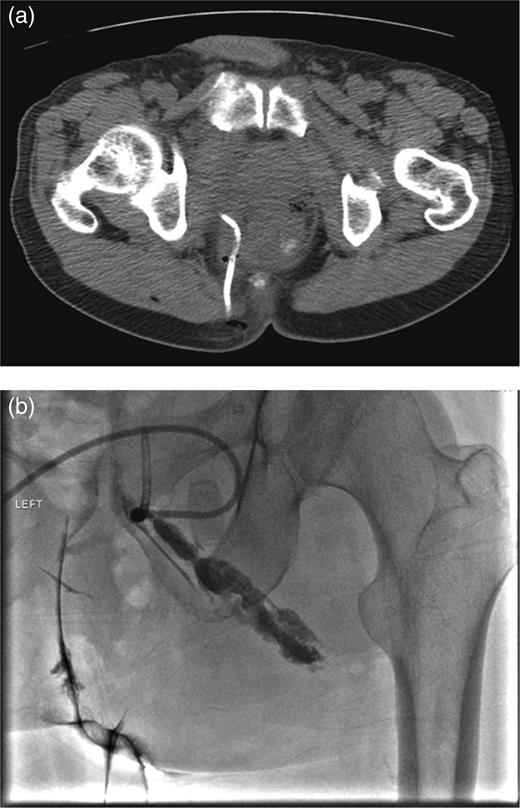

In the 6-week follow-up, repeat CT demonstrated eccentric thickening of the rectosigmoid with interval development of an adjacent complex pelvic fluid collection with supralevator extension measuring 3.5 × 2.5 cm (Fig. 2a and b). Percutaneous needle biopsy revealed pus, and a drainage catheter was left in place (Fig. 3a and b). The patient did not improve, was reimaged and was found to have collection extending into the ischiorectal fossa and supralevator space (Fig. 4). Owing to refractory pain and persistent leukocytosis, the patient was taken to the operating room for examination under anesthesia. No fistulous tract or internal drainage was noted within the rectal vault; however, consistent with the imaging, external induration was observed along the right ischiorectal fossa, where, upon incision, a large purulent cavity was evacuated. On evening rounds, the patient was noted to have a marked leukocytosis and frank stool coming from the ischial wound, and he was taken emergently to the operating room for diagnostic laparotomy where a perforated diverticulum adherent to the pelvic sidewall was identified (Fig. 5). Therefore, a Hartmann procedure, drainage of supralevator abscess, irrigation and debridement of the right ischiorectal wound, was performed.

(a) Repeat CT at 6 weeks showing supralevator abscess formation (white asterisk). The levator ani muscle is illustrated by white arrow (b) coronal image of complex supralevator collection. Arrow points to the levator ani muscle.